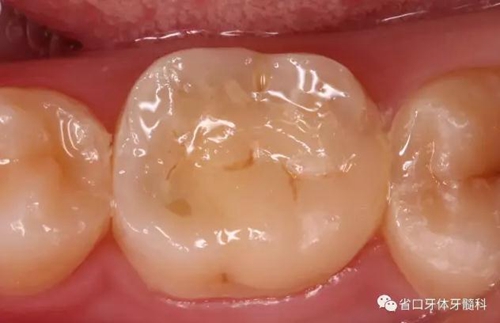

圖3 根管治療術(shù)后4個(gè)月